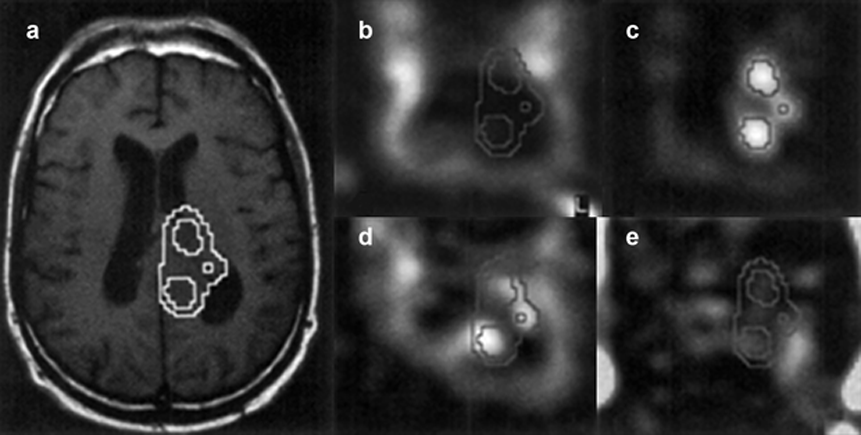

Figura 05-08:

Imagen espectroscópica por RM de protón de un paciente con glioma de alto grado.

(a) Imagen convencional de espín-eco potenciada en T1 sobre la que se muestra el contorno de colina.

Mapas metabólicos de(b) N-acetilaspartato, (c) colina, (d) creatina, y (e) lactato.

El N-acetilaspartato está disminuido en el tumor y en los ventrículos, mientras que el nivel de colina está aumentado en el tumor. Las regiones con aumento de colina no se solapan con regiones que presentan lactato, indicando la localización de las partes activas del tumor.